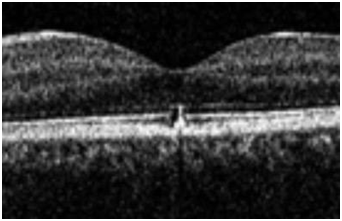

Figure 4 OCT left eye showing retinal pigment epithelial changes.

Figure 4A & 4B Magnified views of left OCT.

Fundus examination revealed retinal pigment epithelial changes on the fovea confirmed by OCT scan which is corresponding with the central scotoma on Amsler grid monitoring. Follow-up examinations revealed reduction in the area of RPE (retinal pigment epithelial hypertrophy) with no or little improvement of visual acuity measured by standardized Snellen or log MAR equivalent. There was no improvement in the area of central scotoma. The mystery remained on the power or class of laser pointer used. The RPE hypertrophy did not warrant any treatment as there was minimal evidence of inflammation and or fluid on the OCT scan. The RPE changes explained the area of scotoma and resolution in the thickness mapping of the subfoveal changes. After follow up of three months the patient who was a Turkish immigrant was lost to follow up (Figure 1–4).